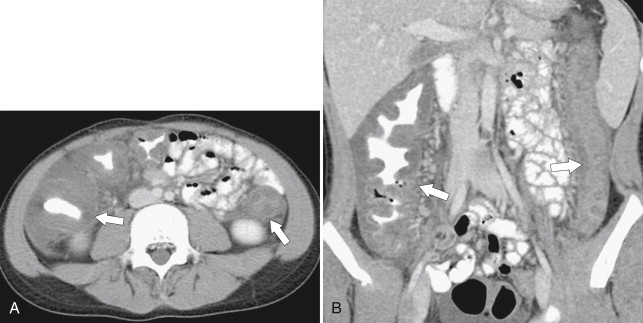

In addition to perforation from toxic megacolon, the greatest risk to patients with chronic UC is the late development of adenocarcinoma of the colon, for which they have an increased risk of 5% to 30% over the general population ( Fig. 5-18 ). The risk increases by 10% for each decade of disease. Patients with more extensive disease may therefore undergo prophylactic colectomy.

Figure 5-18, Axial ( A ) and coronal ( B ) contrast-enhanced CT in a 61-year-old woman with known ulcerative colitis and now an ascending colon adenocarcinoma ( arrows ) with associated lymphadenopathy ( small arrow ).